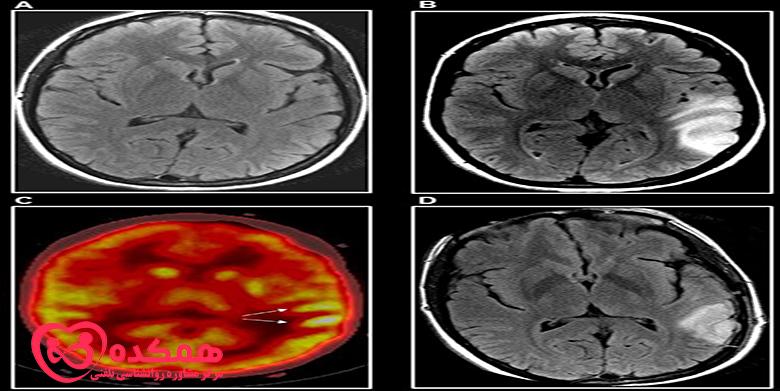

پزشک شما تشخیص صرع را بر اساس سلامت فرزندتان، سابقه پزشکی گذشته و سابقه خانواده شما انجام می دهد. آن ها همچنین یک معاینه فیزیکی دقیق انجام می دهند. و سعی می کنند تا آن جا که می توانند از شما در مورد تشنج های فرزندتان یاد بگیرند. آن ها همچنین ممکن است آزمایش خون انجام دهند. اگر پزشک مشکوک به دیسپلازی قشر مغز باشد، آزمایشات بیشتری تجویز خواهد شد. این ها شامل الکتروانسفالوگرام (EEG) و تصویربرداری رزونانس مغناطیسی (MRI) است.

اگر MRI نرمال باشد، پزشک آزمایشهای تصویربرداری دیگری مانند اسکن توموگرافی گسیل پوزیترون (PET)، SISCOM یا مگنتوآنسفالوگرافی (MEG) را برای تعیین محل وقوع تشنج تجویز میکند. دیسپلازی کانونی کورتیکال به ندرت در سی تی اسکن قابل مشاهده است و گاهی در MRI نیز غیرقابل تشخیص باقی می ماند. در موارد دیگر، ناحیه آسیب دیده که در اسکن MRI نشان داده میشود. در واقع میتواند بزرگتر از چیزی باشد که توسط MRI نشان داده میشود. این می تواند بر نتایج جراحی تاثیر بگذارد.

تست های مختلف تصویر برداری برای دیسپلازی قشر مغز

به همین دلیل، پزشکان از سایر تستهای تصویربرداری قدرتمند مانند ترکیب MRI با وضوح بالا و تست FDG-PET برای شناسایی دیسپلازی قشر مغز استفاده میکنند. تمرکز اصلی درمان دیسپلازی قشر مغز، کنترل تشنج است.